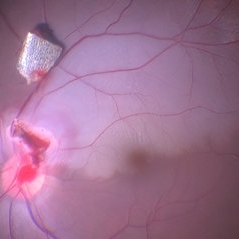

BRAO (3 files)

BRAO (3 files)

BRAO (3 files)

BRAO (3 files)